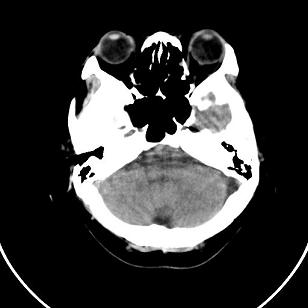

小脑后的囊状低密度影,里面可见分隔,考虑枕大池还是蛛网膜囊肿。

双侧脑室外缘灰质密度结节应该是尾状核的体部;枕大池前缘受压前移位,考虑囊肿

支持灰质移位,mri检查有必要.枕大池蛛网膜囊肿.

1)脑灰质异位。2)双侧枕部颅骨内板下方类似扇形及弧形脑脊样低密度影;鉴别于巨大枕大池与蛛网膜囊肿之间。建议必要时行进一步检查。

支持 1灰质移位,2枕大池蛛网膜囊肿。

支持灰质移位,mri检查有必要.枕大池蛛网膜囊肿